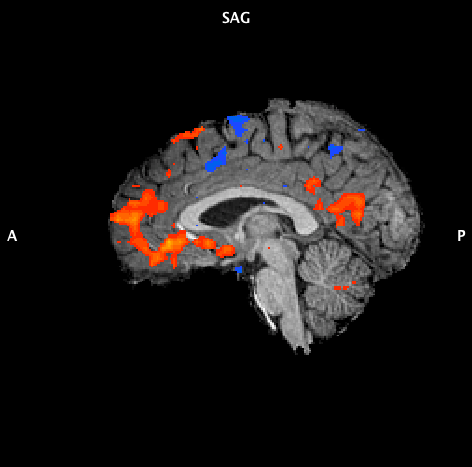

Images 1 and 2 – fMRI scan of my brain not in bliss and bliss

The top image is of my brain when I’m blocking bliss. The bottom image is my brain when experiencing bliss. The red areas are areas of positive connectivity, indicating higher activity. The blue levels of negative connectivity, indicating lower activity. Whilst I am in bliss, you can clearly see the increased level of activity (red) in some areas of the brain and decreased levels of activity (blue) in other areas.

Here is what Dr. Josipovic said:

“The image shows functional connectivity during bliss and during ‘rest/blocking’. The yellow/red areas indicate areas of positive functional connectivity while blue/green indicate areas of negative functional connectivity. The bliss condition resulted in the overall increase of functional connectivity within the default mode network. This is also know as the intrinsic network, responsible for the sense of self and self-awareness. Increased connectivity was especially along its main axis – medial Prefrontal cortex (mPFC) – medial Parietal / Posterior Cingulate Cortex (PCC).“

“The results for the bliss condition could be interpreted as indicating an increased access to subjective pole of one’s experience, and enhanced self-awareness. Impairments in the connectivity between mPFC and PCC have been seen in a variety of disorders, such as ADD. The bliss state may contribute to positive changes in the plasticity of the default network, and may have beneficial effects on one’s attention and self-awareness.”